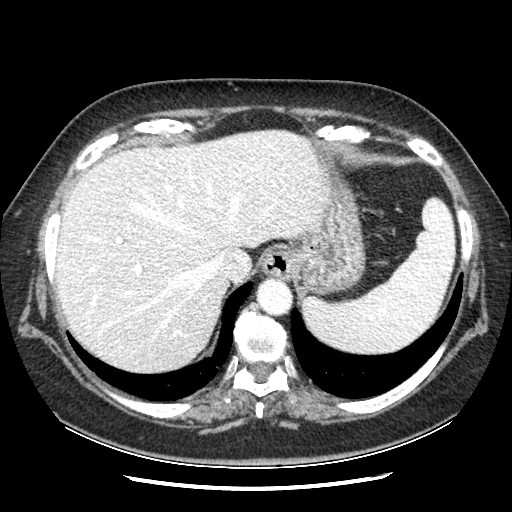

Image Grid

4×3 grid: Rows show different image types (Original NATIVE, Reconstructed NATIVE, Original VENOUS, Generated VENOUS), Columns show windowing techniques (No Window, Lung Window, Mediastinum Window)

Original NATIVE CT scan (input)

Full window (WL 1023.5, WW 4095 → Low −1024, High +3071)

Actual HU range: [-160.0, 240.0]

Original VENOUS CT scan

Full window (WL 1023.5, WW 4095 → Low −1024, High +3071)

Actual HU range: [-160.0, 240.0]